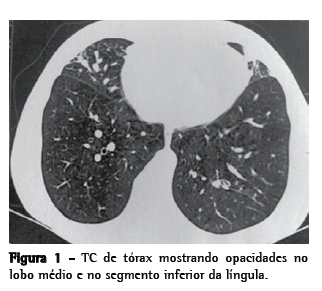

Como persistia a tosse, foi realizada TC de tórax, que evidenciou opacidades em lobo médio, segmento inferior da língula e segmento anterior do lobo superior direito, assim como espessamento das bainhas peribrônquicas, e sinais de impactação mucoide (Figura 1). Em seguida, nova fibrobroncoscopia foi realizada, demonstrando que uma grande quantidade de muco amarelado difuso persistia, e a análise microbiológica revelou o crescimento de Staphylococcus aureus (50.000 UFC/mL).

A TCAR é o melhor exame de imagem para o diagnóstico de pneumonia lipoide, revelando consolidações alveolares, opacidades em vidro fosco, lesões nodulares e espessamento de septos interlobulares e do interstício intralobular.(5) No caso clínico em questão, as alterações da TC de tórax, ainda que associadas às alterações clínicas, não foram suficientes para a conclusão diagnóstica. Prosseguiu-se a investigação, com a análise microbiológica do lavado broncoalveolar, sendo encontrado S. aureus mesmo após o tratamento com ciprofloxacina por 21 dias, e a paciente permaneceu sintomática. A presença de óleo nos pulmões pode predispor a pneumonias recorrentes e, inclusive, a infecções por germes atípicos.(12)